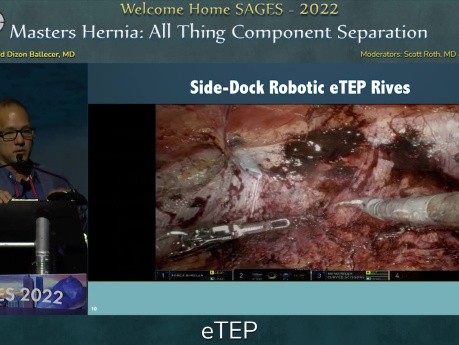

Hernia de Masters: Separación de todos los componentes...

Presentación quirúrgica: Hernia de Masters: Sesión sobre la separación de todos los componentes - eTEP. Esta charla fue presentada por Conrad Ballecer en la sesión "Hernia de Masters: Separación...